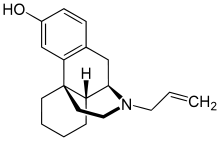

The pharmacodynamic response to an opioid depends upon the receptor to which it binds, its affinity for that receptor, and whether the opioid is an agonist or an antagonist. For example, the supraspinal analgesic properties of the opioid agonist morphine are mediated by activation of the μ1 receptor; respiratory depression and physical dependence by the μ2 receptor; and sedation and spinal analgesia by the κ receptor. Each group of opioid receptors elicits a distinct set of neurological responses, with the receptor subtypes (such as μ1 and μ2 for example) providing even more [measurably] specific responses. Unique to each opioid is its distinct binding affinity to the various classes of opioid receptors (e.g. the μ, κ, and δ opioid receptors are activated at different magnitudes according to the specific receptor binding affinities of the opioid). For example, the opiate alkaloid morphine exhibits high-affinity binding to the μ-opioid receptor, while ketazocine exhibits high affinity to ĸ receptors. It is this combinatorial mechanism that allows for such a wide class of opioids and molecular designs to exist, each with its own unique effect profile. Their individual molecular structure is also responsible for their different duration of action, whereby metabolic breakdown (such as N-dealkylation) is responsible for opioid metabolism.

Several semi-synthetic opioids were developed in Germany in the 1910s. The first, oxymorphone, was synthesized from thebaine, an opioid alkaloid in opium poppies, in 1914.[228] Next, Martin Freund and Edmund Speyer developed oxycodone, also from thebaine, at the University of Frankfurt in 1916.[229] In 1920, hydrocodone was prepared by Carl Mannich and Helene Löwenheim, deriving it from codeine. In 1924, hydromorphone was synthesized by adding hydrogen to morphine. Etorphine was synthesized in 1960, from the oripavine in opium poppy straw. Buprenorphine was discovered in 1972.[228]